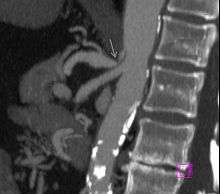

|

Further evaluation and confirmation can be obtained via angiography to investigate the anatomy of the celiac artery.[2] Historically, conventional angiography was used, although this has been largely replaced by less invasive techniques such as computed tomography (CT) and magnetic resonance (MR) angiography.[1][2] Because it provides better visualization of intraabdominal structures, CT angiography is preferred to MR angiography in this setting.[2] The findings of focal narrowing of the proximal celiac artery with poststenotic dilatation, indentation on the superior aspect of the celiac artery, and a hook-shaped contour of the celiac artery support a diagnosis of MALS.[1] These imaging features are exaggerated on expiration, even in normal asymptomatic individuals without the syndrome.[1]

Proximal celiac artery stenosis with poststenotic dilatation can be seen in other conditions affecting the celiac artery.[1] The hook-shaped contour of the celiac artery is characteristic of the anatomy in MALS and helps distinguish it from other causes of celiac artery stenosis such as atherosclerosis.[1] This hooked contour is not entirely specific for MALS however, given that 10-24% of normal asymptomatic individuals have this anatomy.[1]